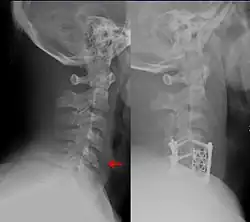

| Teardrop fracture of the cervical spine before and after treatment with metal fixation | |

A flexion teardrop fracture is a fracture of the anteroinferior aspect of a cervical vertebral body due to flexion of the spine along with vertical axial compression.[1] The fracture continues sagittally through the vertebral body, and is associated with deformity of the body and subluxation or dislocation of the facet joints at the injured level.[2] A flexion teardrop fracture is usually associated with a spinal cord injury, often a result of displacement of the posterior portion of the vertebral body into the spinal canal.[3]